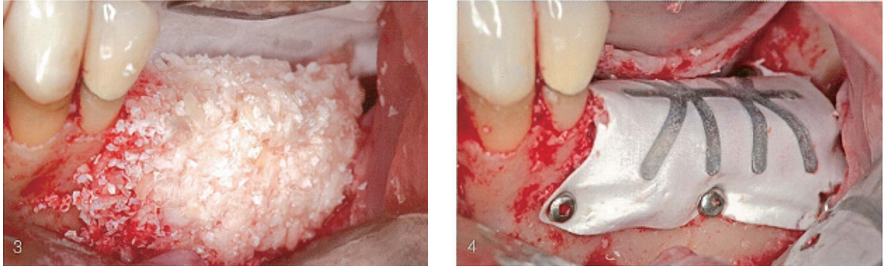

(3)颊侧观,植入混合植骨材料。(4)颊侧观,固定e-PTFE-TR膜。

(5)牙合面观,显示膜和天然牙之间的距离。

(6)颊侧观,天然胶原膜覆盖TR膜。胶原膜用来关闭TR膜和骨之间的缝隙。